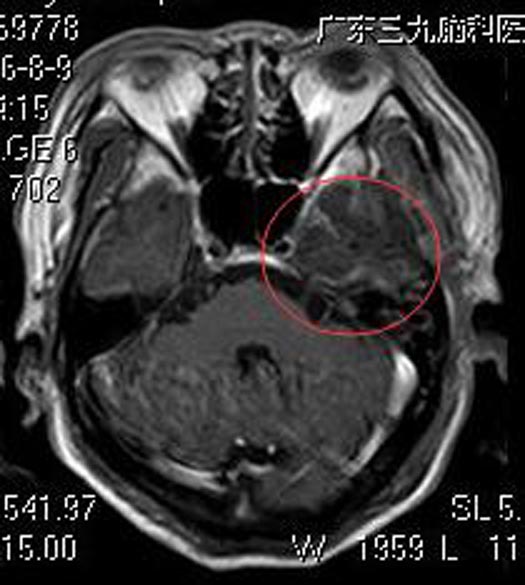

脑肿瘤可不是小事,儿女们认为不能再拖了。广东三九脑科医院头颅MR检查提示:左侧鞍旁三叉神经走行区占位性病变,病变边界清,与左侧三叉神经走行关系密切,大小约2.8cm×3.4cm,增强后病灶呈不均匀强化,其中示多个小环状强化灶,邻近左侧颞叶受压,考虑神经鞘瘤可能性大。

家属要求手术治疗。由综合神经外科鲁明主任主刀,在全麻下行左侧三叉神经鞘瘤切除术,术中显微镜下见病变呈黄白色,质中,三叉神经位于肿瘤前下方,经分离三叉神经保留完整,肿瘤部分跨岩骨位于中颅窝,显微镜下全切肿瘤,过程顺利。术后欧先生未出现面神经损害症状,术后病理结果提示:神经鞘瘤。